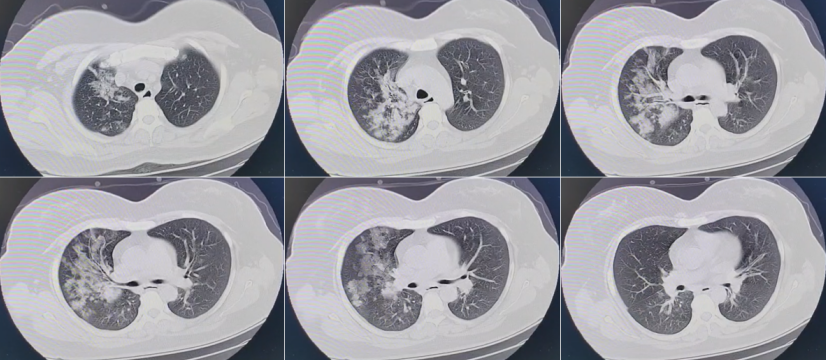

1. 病例一

58岁女性患者,高血压、慢性支气管炎病史,发热伴咳嗽9 d,加重2 d,2022年12月19日入ICU(D9)。12月13日新冠抗原(+),12月17日新冠核酸(+)。入院后给予经口气管插管及机械通气,PEEP 12 cmH2O,FiO1.0,俯卧位通气。血气分析:pH 7.396,PaCO2 38.5 mmHg,PaO2 68.9 mmHg,同时予以其他脏器支持,去甲肾上腺素维持血压。下图为患者发病第8天的胸部CT。

图片

患者2022年12月18日胸部CT

入院后予其标准抗炎治疗,甲强龙40 mg 1周,巴瑞替尼4 mg连用6 d,Paxlovid连用5 d。患者PCT、WBC和CRP均明显下降。

发病第16天(2022年12月26日)复查胸部CT发现病变加重。

患者2022年12月26日胸部CT

患者病变加重无法用继发感染解释。病变的性质和分布更像原发病(病毒感染)所致。所以继续甲强龙(40 mg qd)和巴瑞替尼(4 mg qd)治疗,炎症指标逐渐下降,但影像学仍在进展。遂于VV-ECMO支持下行冷冻肺活检,结果示:肺组织大部分肺泡间隔增宽,间质疏松水肿,纤维细胞及纤维母细胞增生,少量淋巴细胞、组织细胞及个别中性粒细胞浸润,局灶细支气管周上皮化生,伴鳞化,部分肺泡上皮增生,肺泡腔内见组织细胞聚集,少量纤维素、淋巴细胞及个别中性粒细胞渗出,伴机化,较多Masson小体填充,可见透明膜,伴透明膜纤维化;小气道黏膜偶见个别中性粒细胞浸润。符合急性肺损伤增殖期及纤维化期改变。

发病第26天胸部CT示“白肺”。患者最终未能救治成功。

为何影像及氧合加重,出现肺纤维化?我们分析原因,①可能存在抗炎治疗延迟:RECOVERY研究抗炎治疗时间为发病8~9 d(5~13 d)[7],我们的抗炎时间为发病11 d(9~14 d)甚至更长;②可能存在抗炎剂量不足:RECOVERY研究中地塞米松用量为6 mg/d,CoDEX研究中(中重度ARDS)地塞米松用量为10~20 mg/d[8];我们推荐地塞米松6 mg或甲强龙40 mg,但对于重症患者,这种推荐剂量是否合适?③联合:单用激素不能完全抑制炎症反应,需联合托珠单抗和/或巴瑞替尼,具体应如何实施?